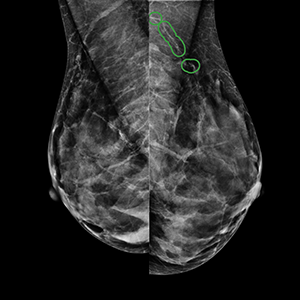

Mammo with Cardiac Screening uses AI technology approved by the FDA to enhance the findings on your screening mammogram by applying a specialized filter to the images. This filter identifies and quantifies calcium deposits in the arteries running through your breast. While breast arterial calcification doesn’t have any effect on your risk for breast cancer, growing clinical evidence shows these calcifications may be an early sign of heart disease.

Mammo with Cardiac Screening is an advanced analysis tool to turn your screening mammogram into a dual purpose study by checking for the presence or absence of calcium buildup in your breast arteries, also known as breast arterial calcification (BAC). In a clinical study published by the Journal of American College of Cardiology (JACC), researchers found that an elevated BAC score is an indication of long-term cardiovascular risk.

Mammo with Cardiac Screening uses AI technology to enhance the findings on your screening mammogram by applying a specialized filter to the images. This filter identifies and quantifies calcium deposits in the arteries running through your breast. While breast arterial calcification doesn’t have any effect on your risk for breast cancer, growing clinical evidence shows these calcifications may be an early sign of heart disease.

Why is breast arterial calcification important?

Heart disease is one of the leading causes of death for women, yet it is often “silent,” showing no symptoms until a major event happens. Clinical research from the Journal of Breast Imaging shows a strong link between calcification in breast arteries with cardiovascular conditions such as coronary artery disease, heart failure, stroke, and peripheral arterial disease. By identifying these markers early, you and your doctor gain a head start on prevention, allowing you to make lifestyle changes or have additional heart screenings conducted.